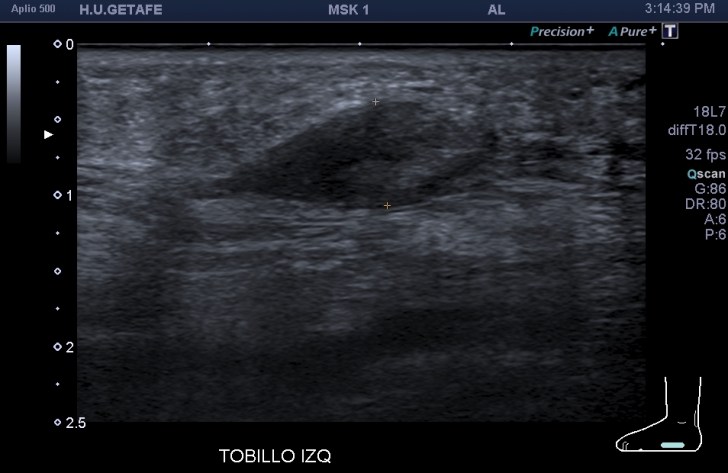

Me llama poderosamente la atención, lo recuerdo perfectamente, la normalidad del recto anterior, pero después de buscar un poco observo como el vasto intermedio si está «distinto», algo heterogéneo, voy a comparar con el lado contralateral y bingo¡ el vasto intermedio, que es de esa musculatura «que nunca tiene nada», modo «ironía on», te sorprende…y la ecografía muscular es como el océano, nunca puedes confiarte…

Mira las imágenes y tu misma te darás cuenta:

La zona que presenta mayor abombamiento y empastamiento (cara lateral del muslo izquierdo), se visualiza aumento del grosor del fascículo muscular correspondiente con el vasto intermedio, sin poder evidenciarse la presencia de lesiones definidas. El diagnóstico es un aumento difuso e inespecífico del Vasto Intermedio, sin masas ni roturas. A valorar con RMN.